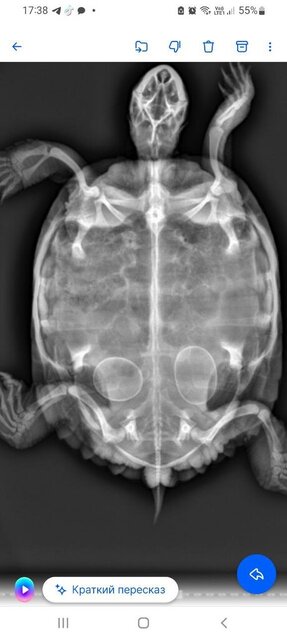

Сделали рентген , видно 2 яйца . в октябре, через 5 недель , ближе к ноябрю , она начала копать везде , фыркать , все нюхать , носится как угорелая , и просится на ручку , вынимала с аквариума ( так как раняла себя и присматривала за ней на ковре , чтобы ее не продуло )